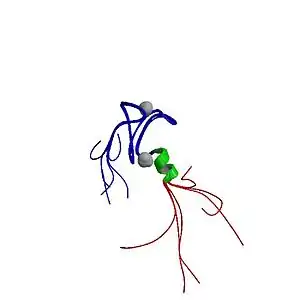

| |

| The autoimmune regulator protein (from the AIRE gene, which causes autoimmune polyendocrine syndrome type 1 when non-functional) | |